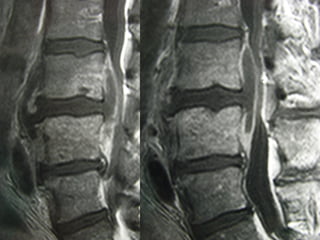

MRIMRI